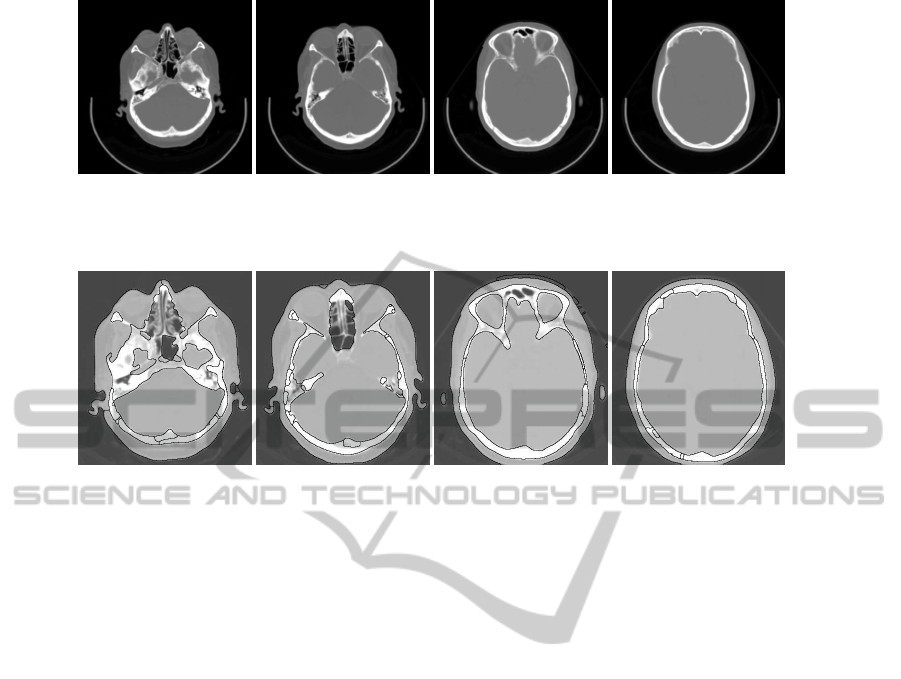

Brain segmentation in head computed tomography scans is essential for the development of computer-aided

diagnostic methods for identifying the brain diseases. In this paper we present a hybrid framework to brain

segmentation which joints region-based information based on watershed transform with clustering techniques.

A pre-processing step is used to reduce the spatial resolution without losing important image information. An

initial partitioning of the image into primitive regions is set by applying a rainfalling watershed algorithm on

the image gradient magnitude. This initial partition is the input to a computationally efficient region segmenta-

tion process which produces the final segmentation. We have applied our approach on several head CT images

and the results reveal the robustness and accuracy of this method.